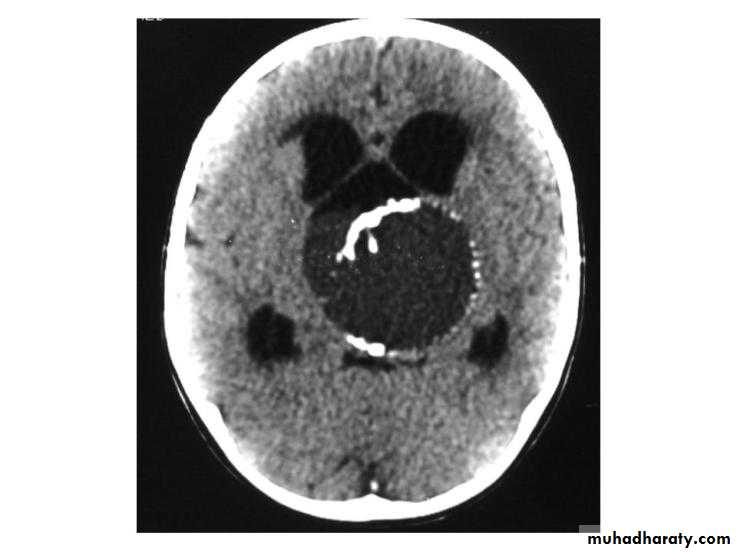

Craniopharyngiomas: arise from the remnant of the buccal ectoderm of the pharyngeal pouch , can present at any age 90% are cystic containing dark brown fluid like engine oil , full of cholesterolclinically presented by visual disturbances as bitemporal hemianopia with hydrocephalus

CT scan will show mixed hyper and hypodense lesions , with cystic components with or without hydrocephalus.RX is usually surgical by craniotomy or trans-sphenoida approach.

CRANIOPHARYNGIOMA (INTRA-OPERATIVE) / CT-SCAN